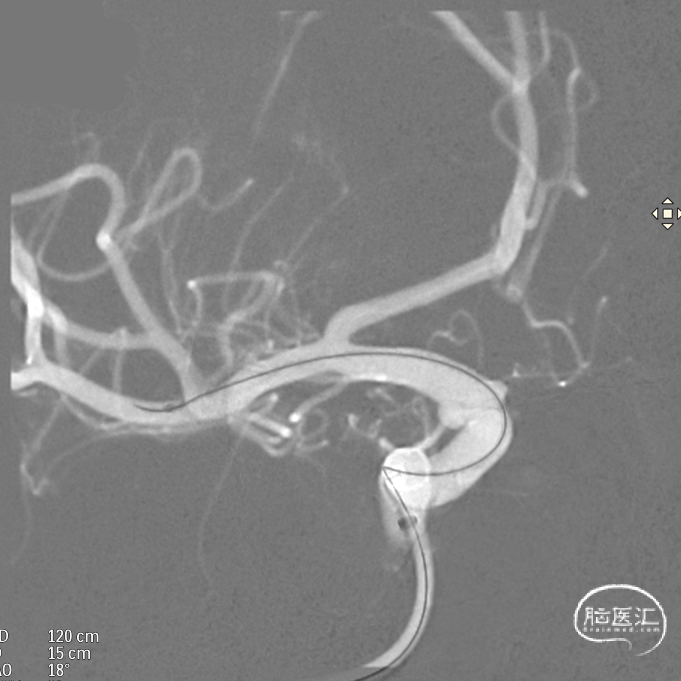

微导管到位:Synchro微导丝引领支架微导管通过病变血管进入大脑中动脉M1段远端。

支架到位,远端打开(正侧位):4.75-20mm支架在大脑中动脉M1段打开,回撤至C6段远端锚定。支架释放过程中,轻柔推送支架系统,可见支架导管沿血管壁大弯侧走行,支架打开良好。

支架中段打开: